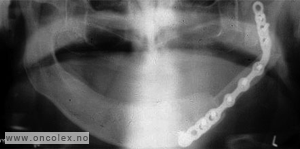

Røntgenbilde av graft fra leggbenet som fikseres med metallskinne.

Transplantatet fra leggen tilpasses underkjeven og festes med plater på hver side. Blodkar på transplantatet syes til blodkar på halsen. Bløtdelene over graftet  lukkes enten primært med slimhinne, eller dekkes med fullhud fra graftet, eventuelt med delhud på muskel/bløtdeler.